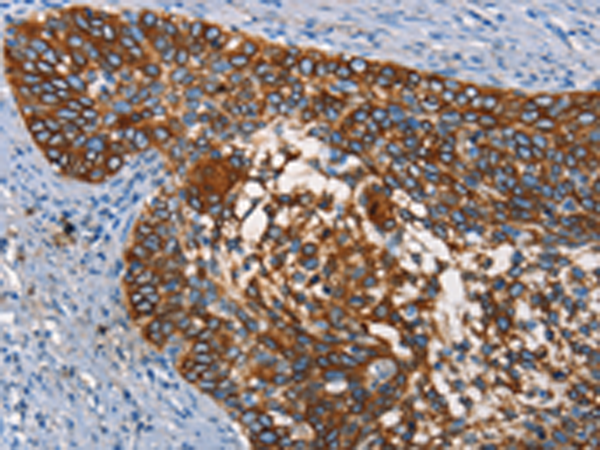

分类: 科研抗体货号: P11248别名: TKT; MIG20a; NTRKR3; TYRO10应用: IHC反应种属: Human, Mouse